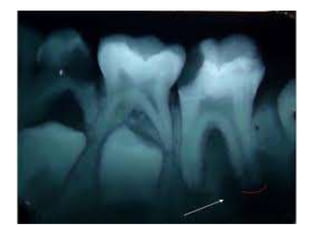

Incorrect Horizontal

Angulation: overlapped

contacts. Cause: central ray

not directed through inter

proximal spaces. Correction:

rimm alignment device .

Vertical angulation is too flat.

Insufficient angulation

Incorrect Horizontal Angulation: overlapped contacts.Cause: central ray not directed through inter proximal spaces. Correction: rimm alignment device . Vertical angulation is too flat. Insufficient angulation